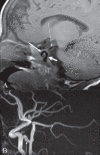

Moya moya appearance

Moya moya is a Japanese term that means ‘puff of smoke.’ It represents the angiographic appearance of basal telangiectasias, which consist of dilated collateral branches of the lenticulostriate and thalamostriate arteries [Figure 12A and

andB

B].[14] It is usually seen in the anterior circulation in association with internal carotid artery stenosis. When the moya moya appearance is seen along with idiopathic occlusion of the internal carotid arteries it is called moya moya disease; when the occlusion is secondary to some other disease it is called moya moya syndrome. Causes of moya moya syndrome include NF1, sickle cell disease, bacterial meningitis, polyarteritis nodosa, radiation therapy, tuberculosis, and atherosclerosis. Histopathology of occluded arteries in moya moya disease shows endothelial hyperplasia and fibrosis without inflammatory reaction.[14] Children with moya moya usually have ischemia or infarction, while adults with moya moya usually have hemorrhage. The treatment of moya moya includes anticoagulation, hypertransfusion, encephalo-duro-arterio-synangiosis (EDAS), anastomosis of the superficial temporal artery with the intracranial arteries, and sympathectomy or cervical ganglionectomy.

Figure 12 (A, B)

caption a4

Moya moya appearance. Lateral anterior oblique view (A) of an internal carotid artery (thick short arrow) angiogram shows multiple, small, tortuous collateral vessels in the distribution of the middle cerebral artery (arrows), suggestive of the moya moya …